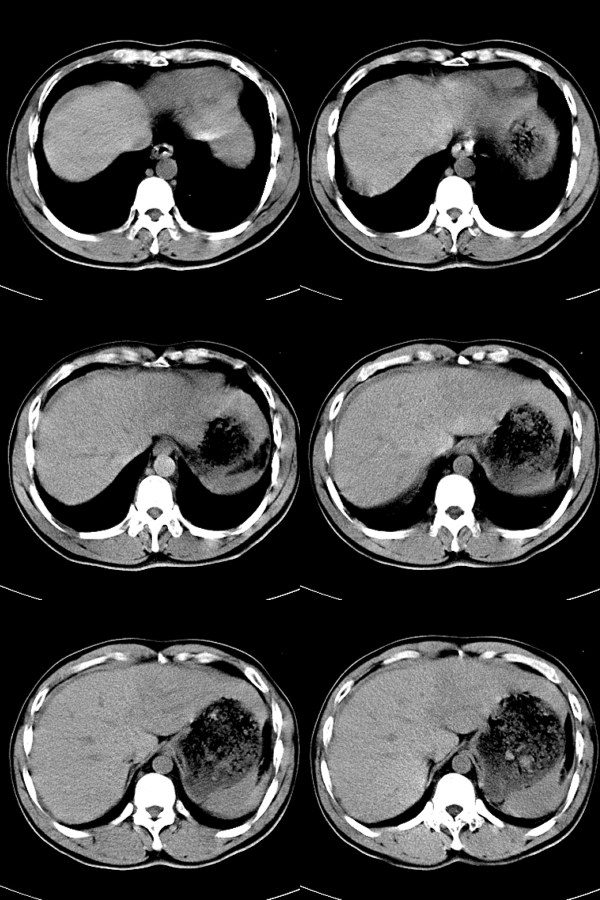

标题: CT17991:M32y,腹部外伤。

32岁男性,外伤后腹部、腰部疼痛。腹部压痛明显,呈“板状腹”。既往体健。

血肿,脾破裂。

考虑脾破裂并腹腔积血。

脾破裂并腹腔积血。

考虑脾脏破裂

脾破裂伴腹腔积血。

脾破裂并腹腔积血.大网膜血肿或积血